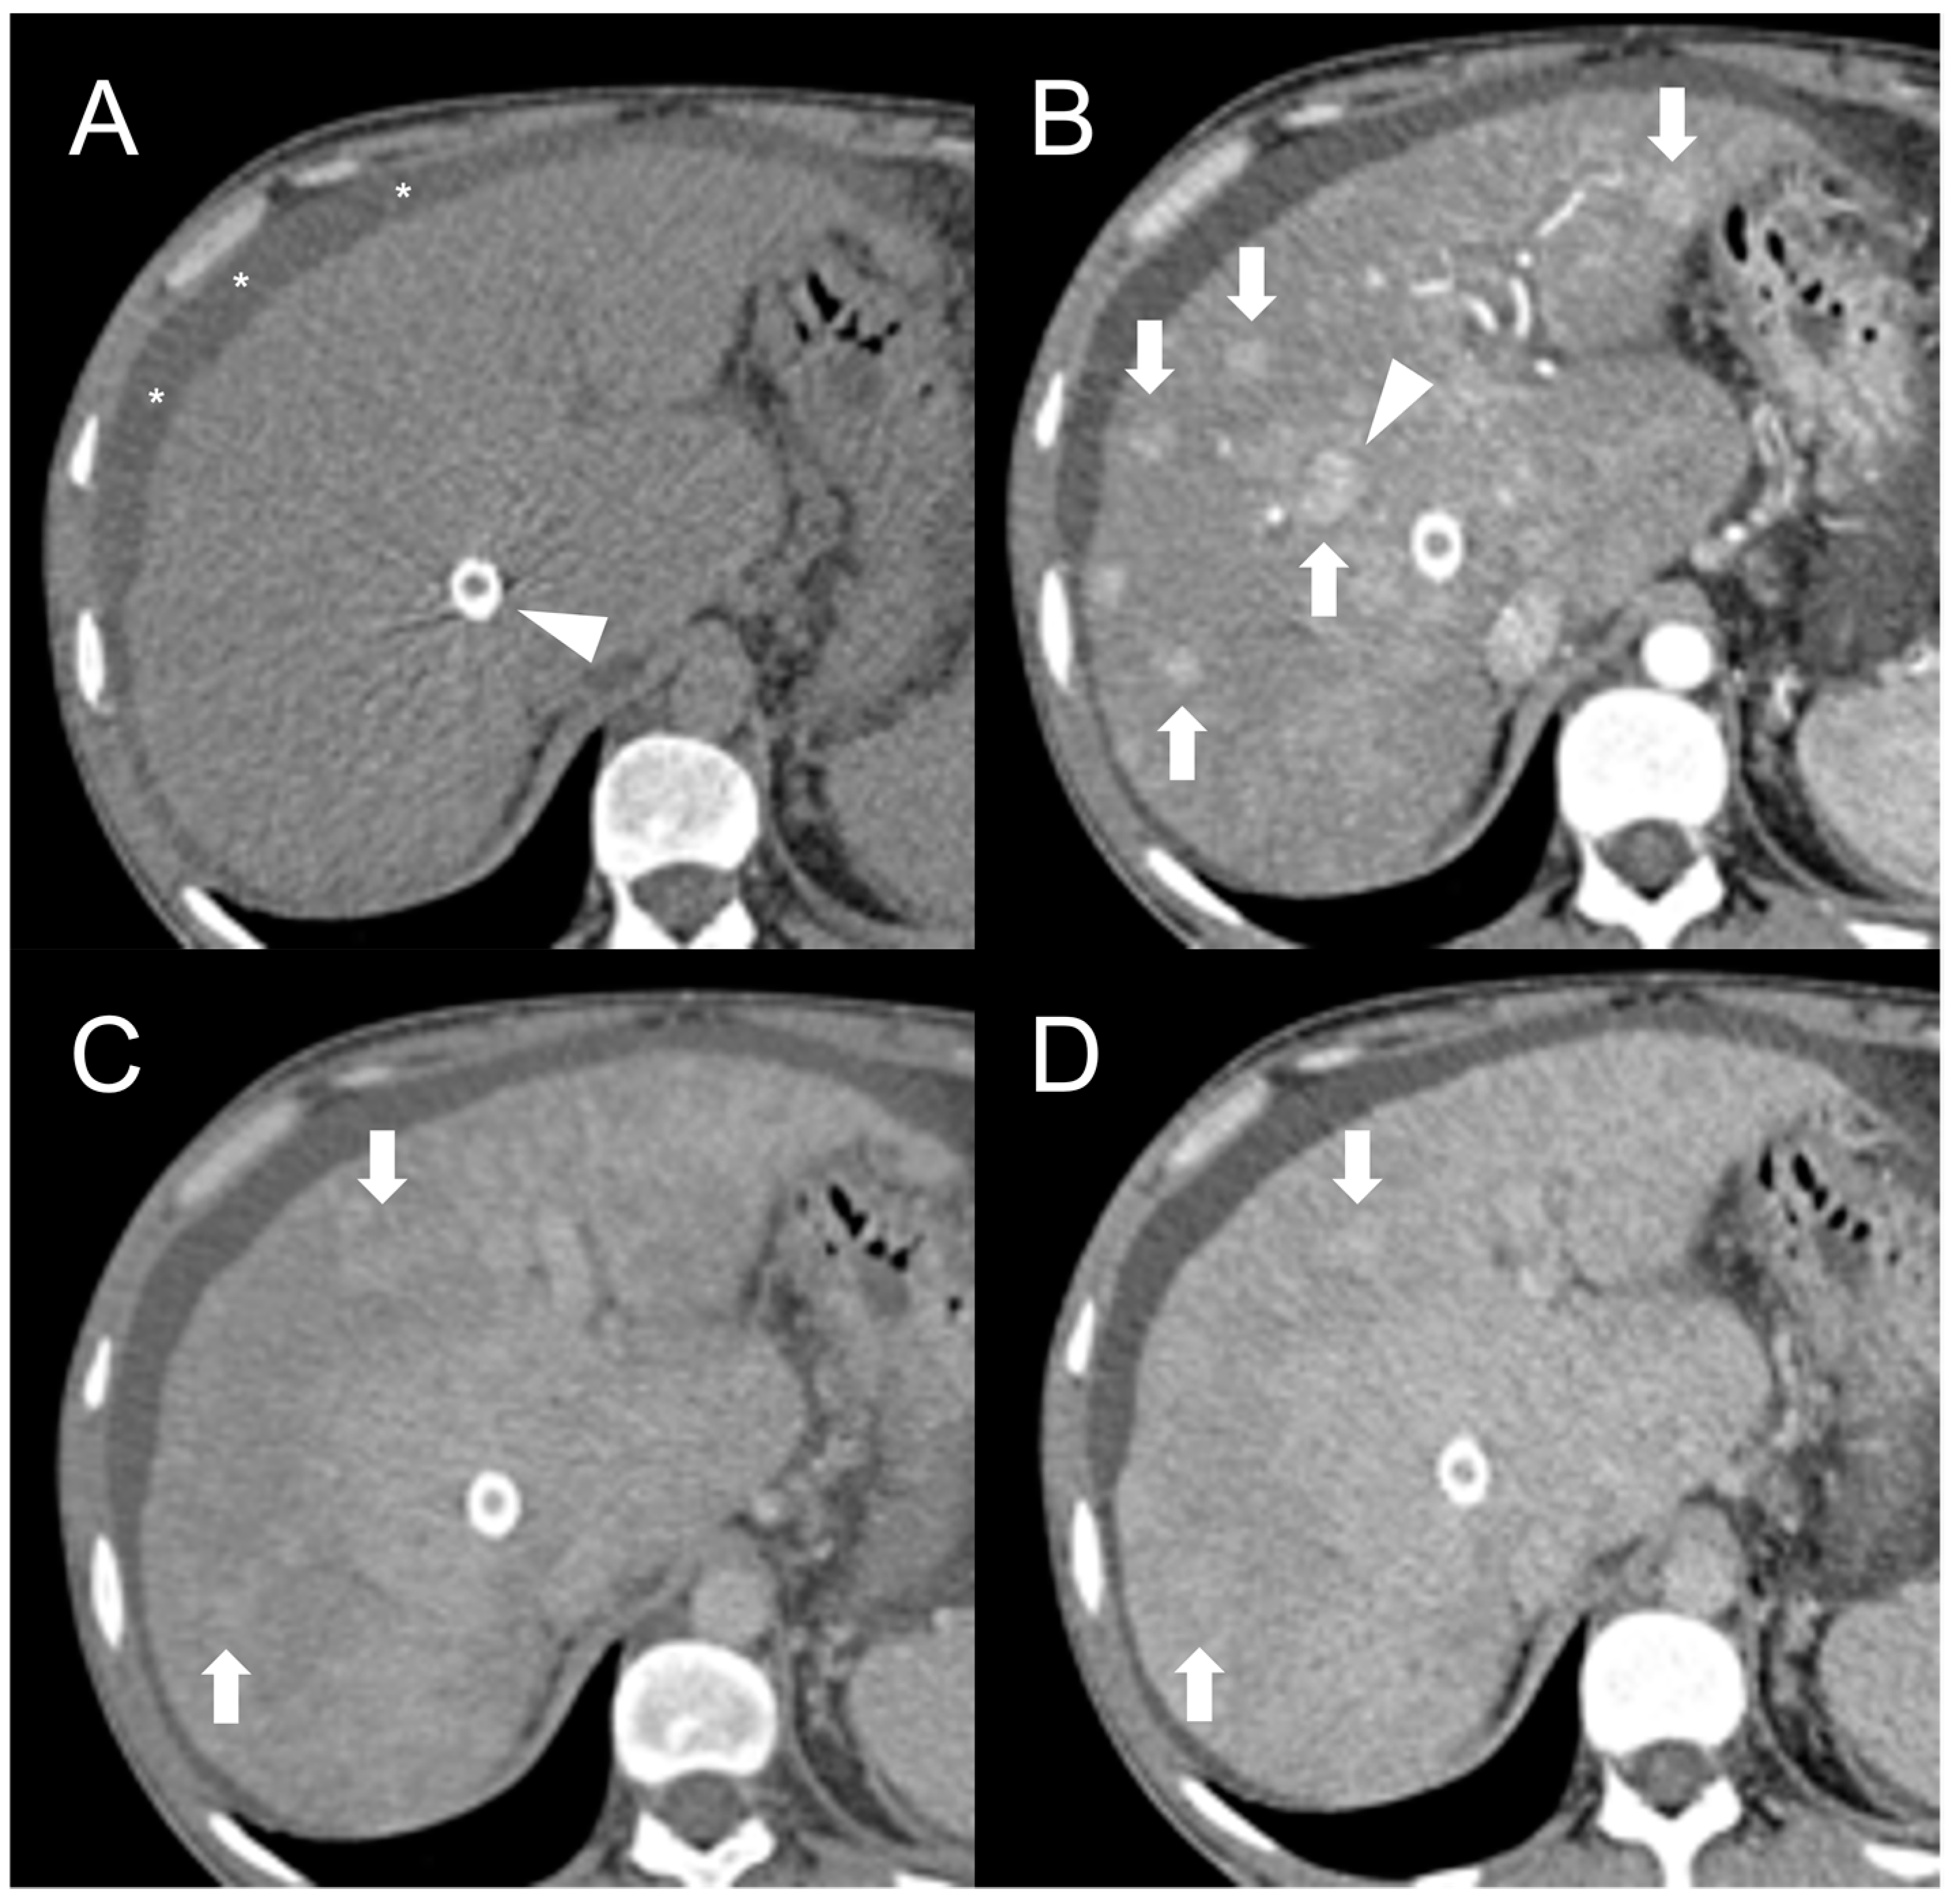

Figure 1.

CT examination of 36-years-old male patient with Budd–Chiari syndrome. On unenhanced images (A), the liver parenchyma appears relatively homogeneous, and the presence of TIPS stent (arrowhead) and perihepatic ascites (asterisks) can be observed. On arterial phase (B), multiple homogeneously enhancing FNH-like RNs can be visualized in the liver (arrows), some exhibiting a hypodense perinodular rim (arrowhead) due to atrophic hepatic tissue with congested sinusoids. In both portal venous (C) and delayed phase (D), the regenerative nodules (arrows) become iso-dense or slightly hyperdense compared to the surrounding inhomogeneous liver parenchyma, making them difficult to detect.

After iodine contrast administration, the nodules are well evident on arterial phase images because they are hypervascularized, hence showing marked and homogeneous contrast enhancement in almost all cases (Figure 1B). Hypervascularization is atypical in cirrhotic regenerative nodules, but in FNH-like RNs associated with BCS it probably represents a compensatory response to regional loss of portal flow. On the portal and late venous phases, the FNH-like RNs usually remain isodense or slightly hyperdense (Figure 1C,D). A hypodense perinodular rim may also be observed on contrast enhanced CT imaging because of the presence of atrophic hepatic tissue around the nodule with sinusoidal congestion.

CT features of FNH-like RNs frequently change during follow-up. According to a retrospective longitudinal study by Flor et al. [15], nodules that were small (<15 mm) and homogeneously enhancing in the arterial phase became larger and showed a heterogeneous enhancing pattern, often with washout and a central scar, in 42% of cases after three years from detection.